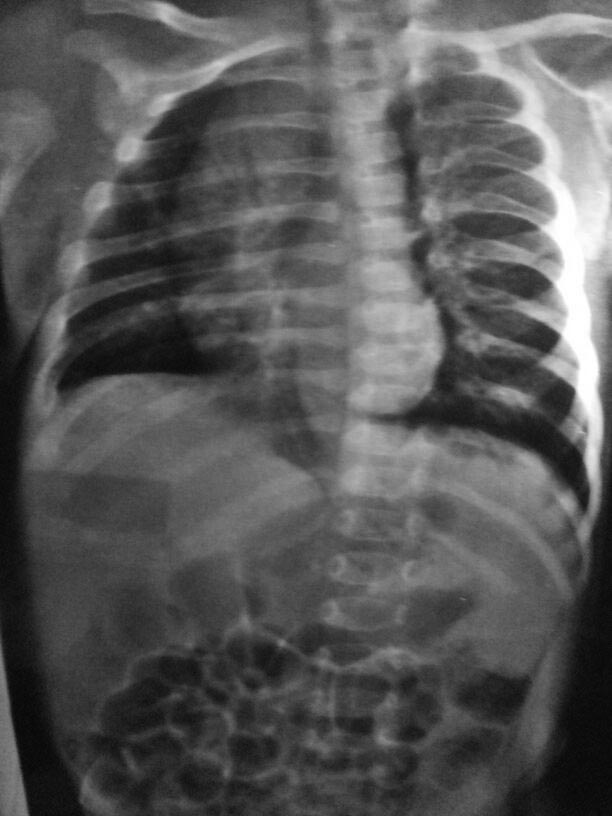

Здравствуйте уважаемые коллеги. Ребенок возраст 45 дней, поставлен

диагноз врожденный сколиоз первой ст. Прошу.., кто сталкивался с такими

пациентами., помочь в тактике лечения.